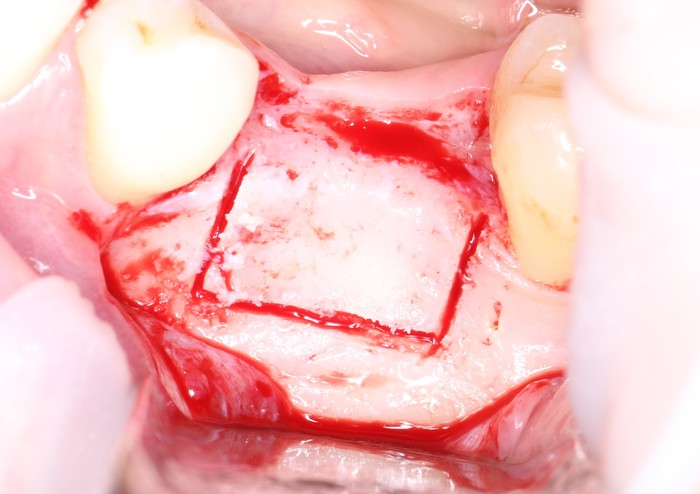

После того, как анестезия подействовала, при помощи скальпеля производится разрез, а с помощью распатора – скелетирование кости. (отделение надкостницы от компактного вещества кости)

Разрез:

Скелетирование кости:

При помощи ультразвукового наконечника выделяется костный фрагмент,

а специальных остеотомов – отделение этого фрагмента от челюсти:

Остеотом необходимого размера помещается в щель, сделанную ультразвуковым наконечником, а дальше производится расклинивание.

Размер блока должен соответствовать размерам области, которую необходимо восстановить (между зубами около 20мм.):

Примеряемся:

Поэтому ультразвуковым наконечником необходимо эту пластинку убрать.

Так она выделяется:

А удаляется теми же остеотомами:

Примеряем наш блок: